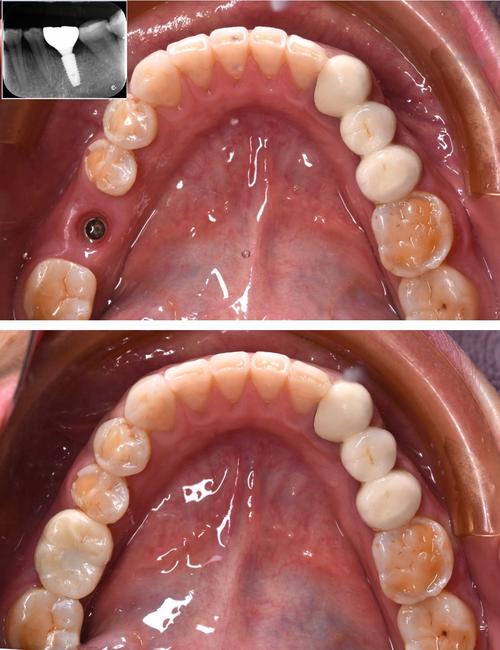

同福医植牙效果的最终体现,是让患者获得“以假乱真”的口腔修复体验,在功能层面,种植体通过基台与牙冠连接,形成独立支持结构,咀嚼效率可恢复至天然牙的90%以上,患者可正常进食坚果、排骨等硬物,无需担心脱落或损坏,美观层面,医生会根据患者的面部轮廓、肤色、邻牙形态及牙龈弧线,个性化设计牙冠的形态、大小及颜色,确保与邻牙色泽过渡自然,牙龈边缘无黑线,微笑时协调美观。

稳定性方面,成功的骨结合使种植体成为“天然牙根”,可承受垂直及侧向咬合力,不会像活动假牙一样基托压迫牙龈,避免黏膜萎缩及异味问题,临床数据显示,同福医种植的10年存留率达95%以上,部分患者使用15年以上仍功能良好,真正实现“一次种植,终身受益”。